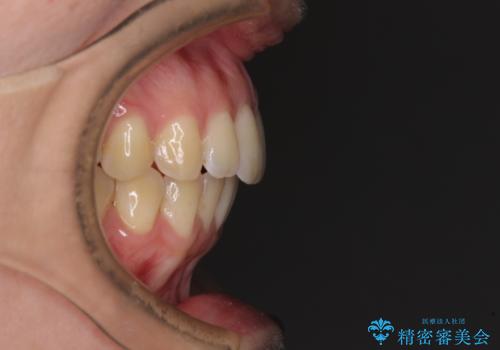

前歯のデコボコを解消 インビザラインによる矯正治療

- 上下前歯のデコボコと深い咬み合わせを気にして来院された患者様です。

インビザラインによる上下歯列の拡大と、IPR(歯と歯の間を削る)にるスペースの獲得により、前歯のデコボコを改善することとしました。

上の前歯をもう少し整えたかったのですが、患者様の治療を早く終了させたいという希望により、細かい叢生を残しての終了となりました。